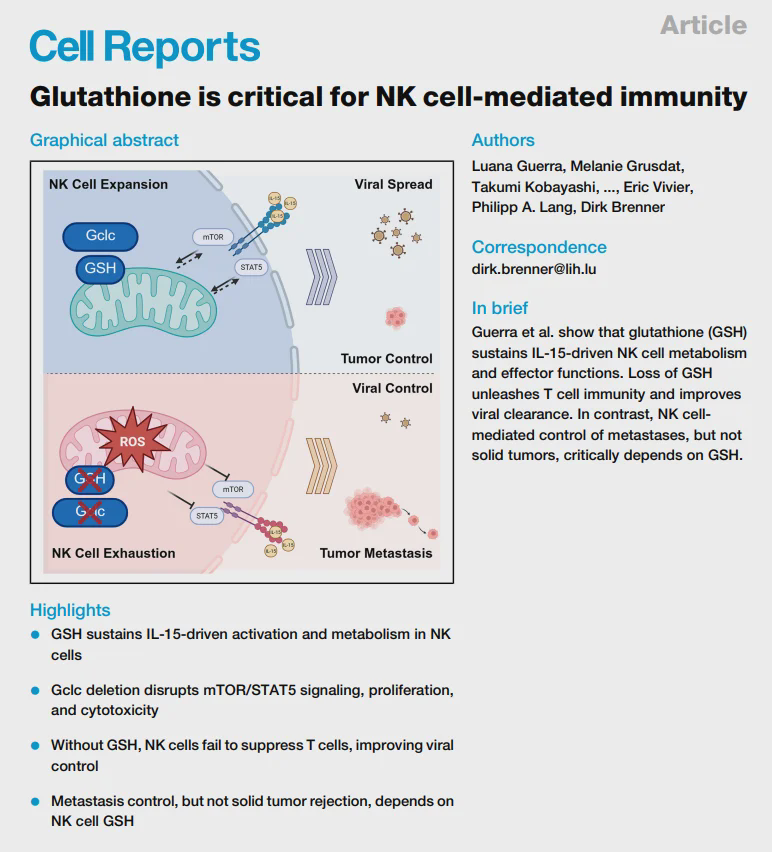

Glutathione is even more powerful! Latest research shows: Without it, immune cells become paralyzed and tumor metastasis becomes uncontrollable!

Amino acids are crucial in the initiation, progression and resistance of tumors. The limited supply of amino acids in the tumor microenvironment restricts their acquisition, and this has become a promising anti-tumor strategy. Cysteine has